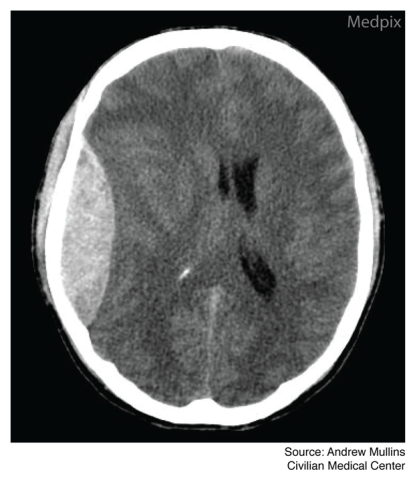

Neurologic examination shows that the patient is unresponsive to verbal or painful stimulation, and eye examination shows a fixed and dilated right pupil. The patient is subsequently intubated. Plain radiograph films of the lateral cervical spine show no acute abnormalities with visualization of C7–T1. A CT scan of his head is shown.

CT scan

All patients diagnosed with an acute symptomatic (i.e., unresponsive, bradycardia, bradypnea, and hypertension) epidural hematoma on non-contrast head CT following a traumatic head injury should be managed with emergency craniotomy to evacuate the hematoma and lower ICP. This procedure provides the best means of rapidly evacuating the hematoma and preventing the impending brain herniation.

Choice A. Observation with serial CT scans is the correct course of action for a neurologically and hemodynamically stable patient that is diagnosed with an acute epidural hematoma but showing no evidence of increased intracranial pressure (ICP). However, the patient in this vignette is not stable and requires emergent surgical management to evacuate the hematoma and rapidly lower elevated intracranial pressure.